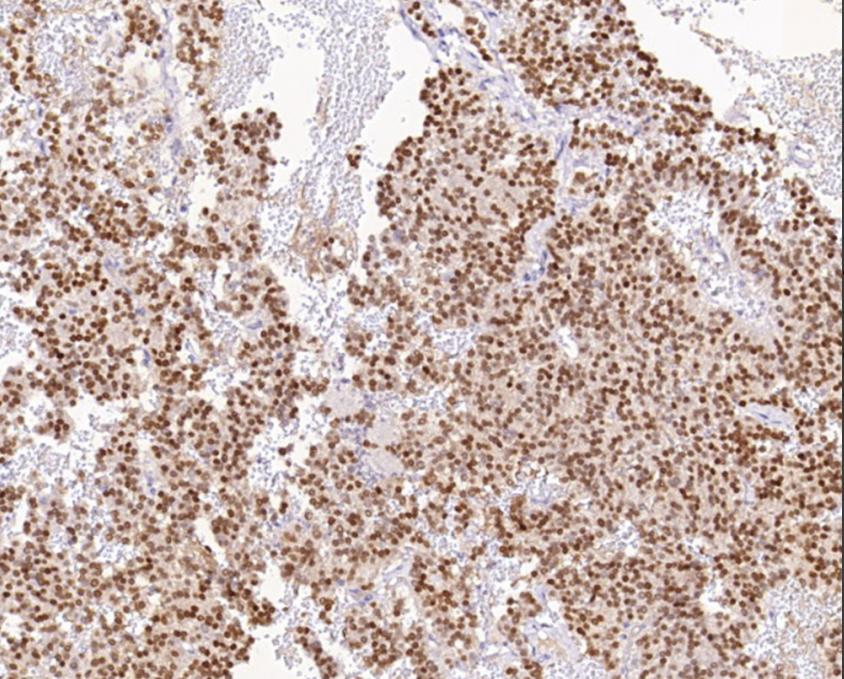

Tissue: paraffin section

Positive control: Pituitary tissue

T-PIT is a member of the T-box transcription factor family 19, which specifically regulates the expression of opioid-pituitary melanocyte-stimulating hormone (POMC) and plays an important role in the differentiation of adrenocorticotropic hormone cells. High expression of T-PIT in pituitary tumors indicates differentiation of the adrenocorticotropic hormone cell lineage.

T-PIT antibody reagents can specifically bind to T-PIT molecular antigens. Immunohistochemistry kits containing T-PIT antibody reagents are suitable for the precise diagnosis of pituitary adrenocorticotropic hormone (ACTH) cell adenomas.